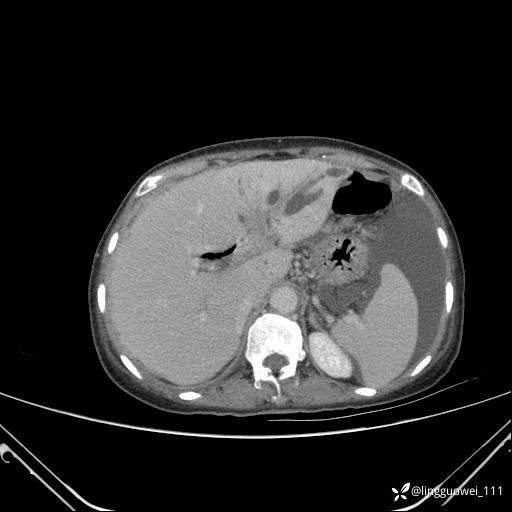

病例女,65岁,门诊行胃肠镜检查后,说腹胀入院检查,CT能发现病因吗?已公布结果

主诉:门诊行胃肠镜检查后,诉腹胀,入院检查,肝有病变吗?腹膜及腹腔的表现有特征性吗?

增强动脉期:

img